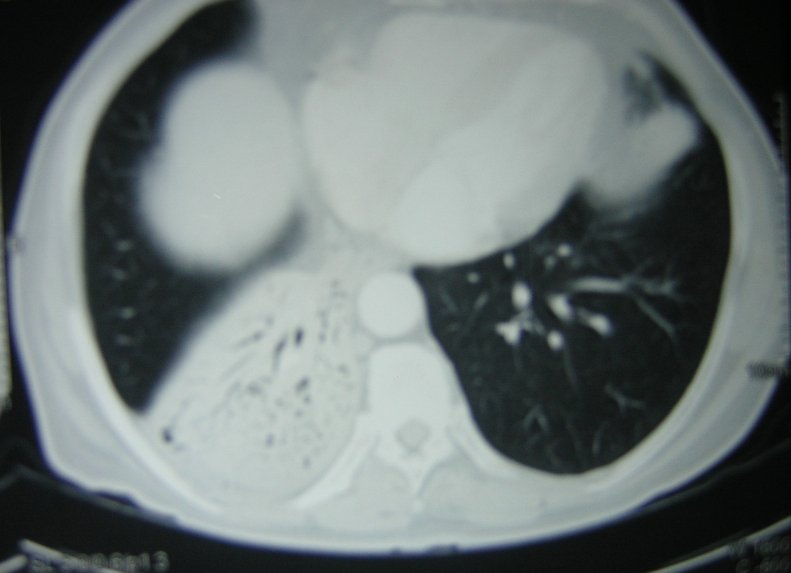

A computerized tomography (CT) scan ofthethorax (figure 6) showed consolidation in the right lower lobe. There was no hilar or mediastinal lymphadenopathy or narrowing of the right lower lobe bronchus.

Figure 6: CT scan of the thorax showing air bronchogram in the right lower lobe